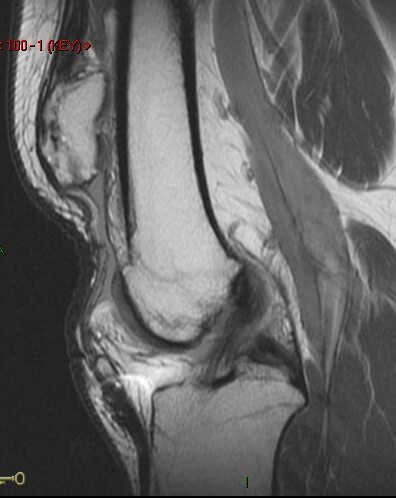

27 y/o patellar tendon rupture with repair 2 years ago. Re-injury 1 year ago. Now with increasing pain and limited range of motion.

Figure 2 for case Patellar tendon re-tear

Figure 2

The acute changes have resolved but the patient has a re-tear of the tendon. The patella is retracted superiorly. Important to measure the length of gap as well as any residual tendon for surgical planning.

Patellar tendon re-tear